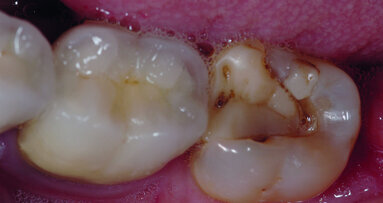

Les dents postérieures acquièrent de la résistance lorsque la zone de crête marginale et la face proximale représentent la structure dentaire naturelle et n’ont pas été restaurées. Les dents ayant subi un traitement endodontique – dans une situation où, soit une carie occlusale affecte les puits et sillons avec atteinte de la pulpe, soit une ancienne restauration au composite ou à l’amalgame et de taille petite à moyenne est présente – nécessitent une restauration conservatrice (Fig. 9). Ces dents peuvent être restaurées après élimination du matériau de restauration existant et du matériau d’obturation de la cavité pulpaire, y compris du canal sur une longueur de 2,0 à 3,0 mm.

La mise en place d’un composite classique collé dans la dent fournit une solution de restauration satisfaisante et durable à ces dents, et une couronne n’est généralement pas nécessaire. La préparation d’accès ou la restauration existante, devrait laisser intacte la plus grande partie de la largeur cuspidienne. Lorsque la préparation qui suit l’élimination de la carie et des matériaux de restauration existants envahit la largeur de la cuspide et mène à l’absence de la moitié de cette structure dentaire, une restauration plus importante est indiquée.